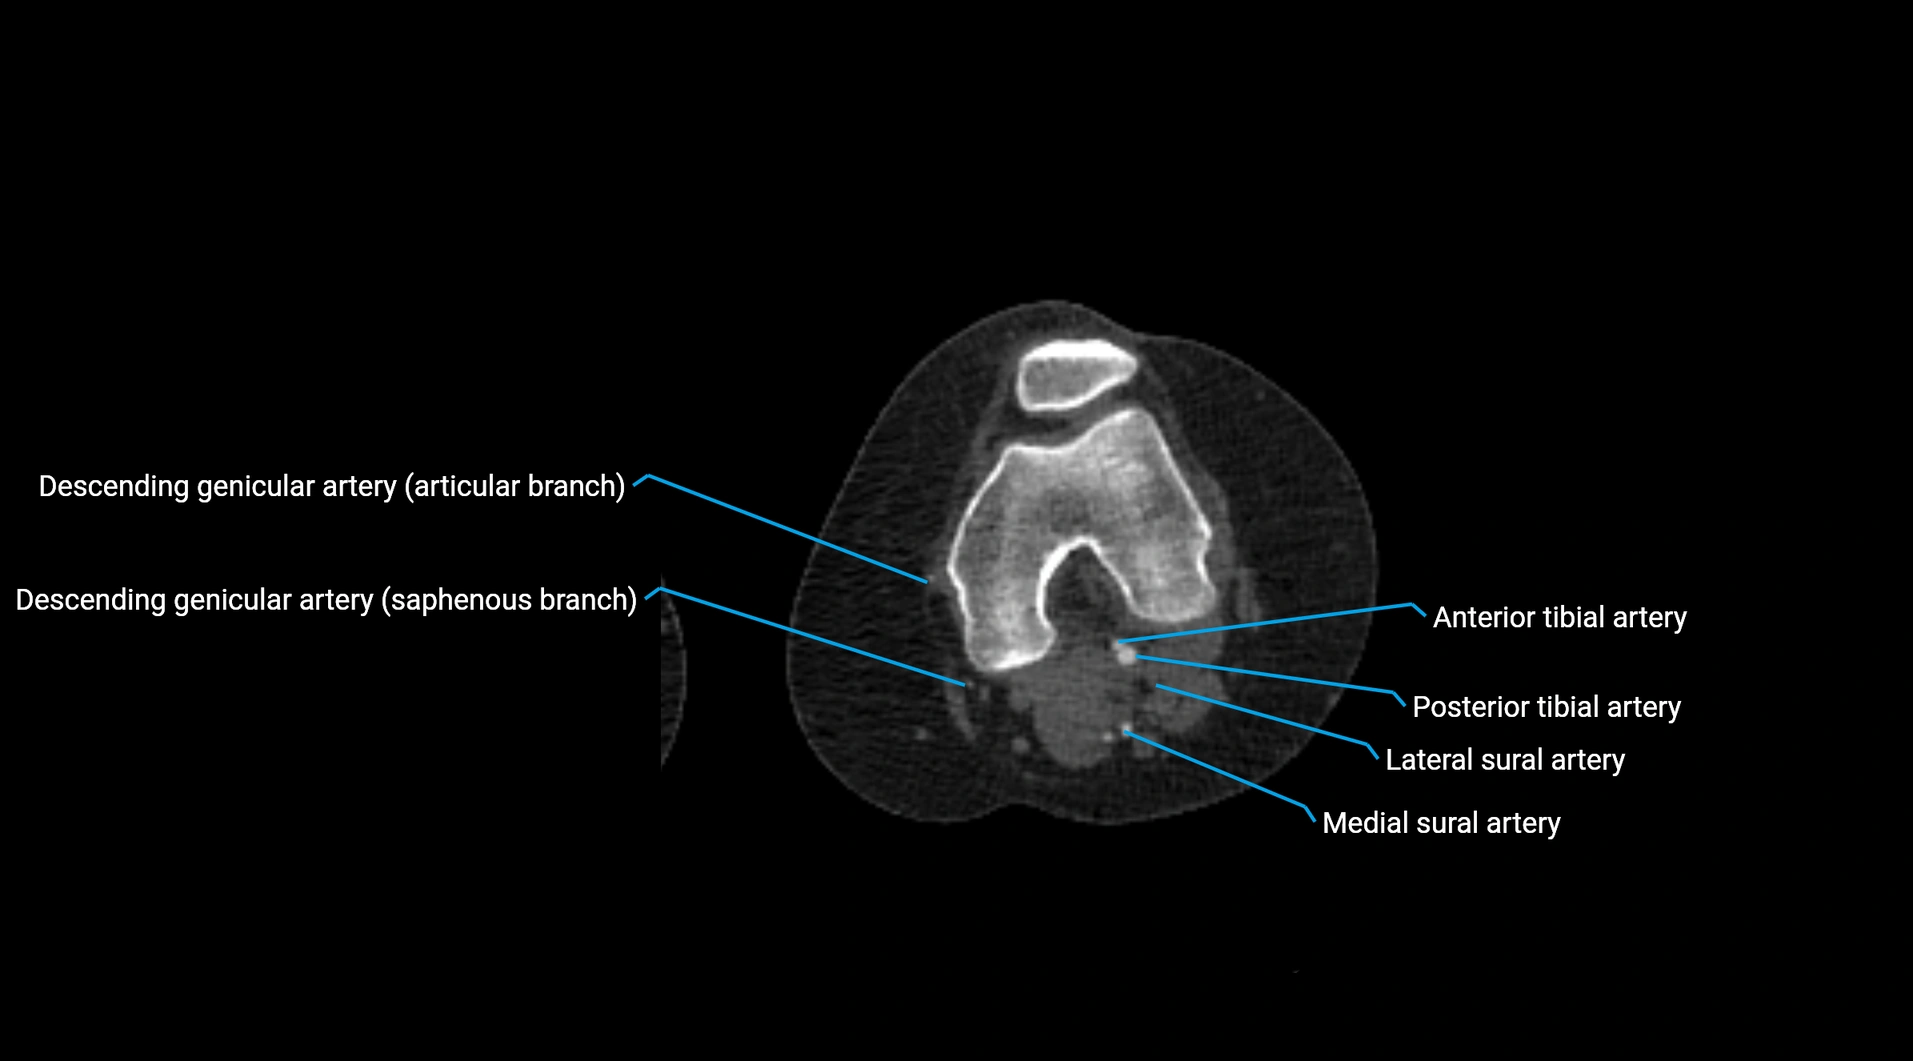

Contrast-enhanced CT (CTA):

• Gold standard for abdominal aortic imaging

• Provides excellent detail of lumen, wall, aneurysm, thrombus, and branch vessels

• Multiplanar and 3D reconstructions help in aneurysm measurement, stent graft planning, and dissection evaluation

• Detects acute rupture, traumatic injury, or occlusion with high sensitivity